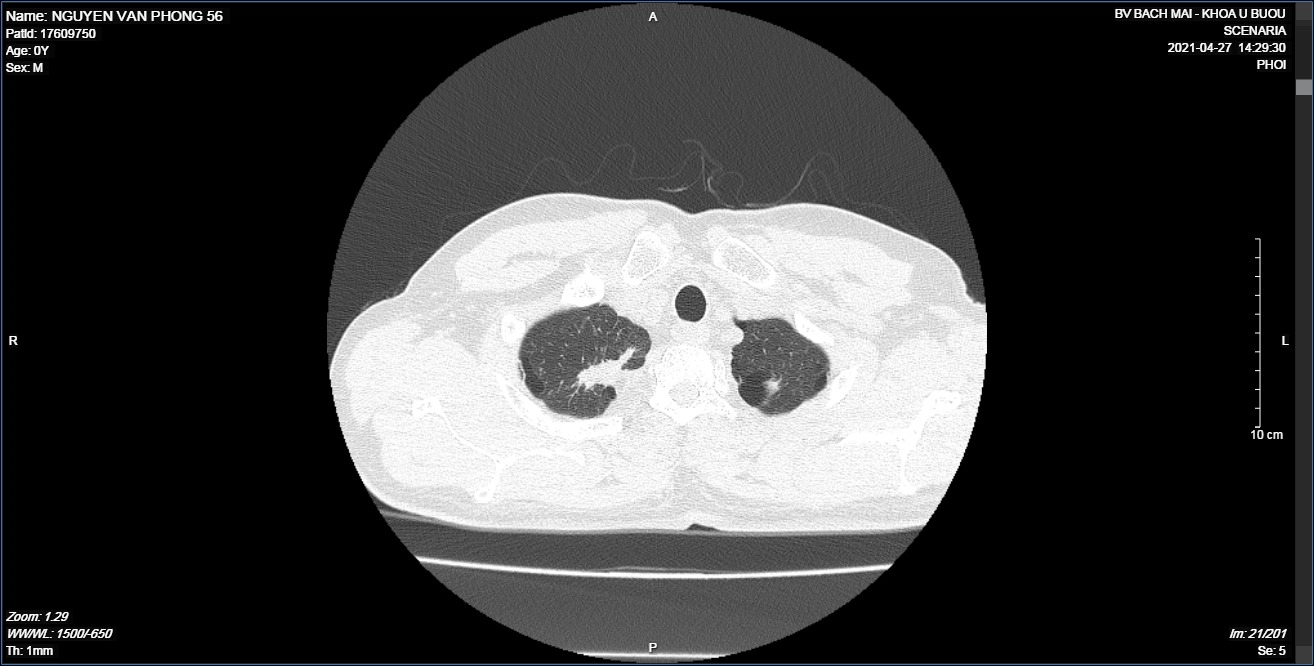

Chụp cắt lớp vi tính lồng ngực sau điều trị: Hình ảnh khối u thùy trên phổi phải kích thước 3×2 cm

Trước điều trị: Hình ảnh khối u thùy trên phổi phải kích thước 5x6cm

Sau điều trị 6 tháng: Hình ảnh khối u thùy trên phổi phải kích thước 3×2 cm

Sau điều trị 9 tháng:

Hình ảnh khối u thùy trên phổi phải kích thước 1×2 cm.